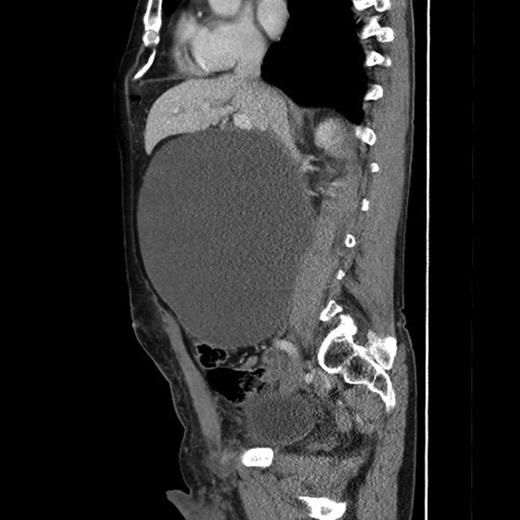

The CT (Figs 1–3) was performed identifying a unilocular, cystic lesion arising from within the right side of the abdomen. This lesion was distinct and not found to be related to any of the intra-abdominal organs. The radiological dimensions of the lesion were 22 × 20 × 19 cm. There were no radiological features to suggest acute or chronic pancreatitis. The findings were explained to the patient, and he was booked for laparotomy and excision of the cyst.

Axial slice from the CT imaging identifying the retroperitoneal pseudocyst.